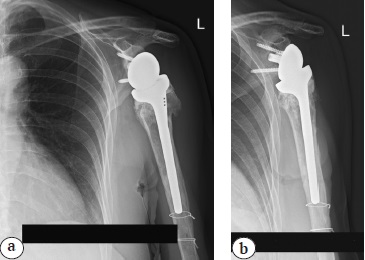

A 73-year-old patient applied to the European Clinic of Sports Traumatology and Orthopaedics (Mocow) 4 days after the injury resulting from a fall on the left upper limb. An X-ray examination was performed on admission, a multi-fragment fracture of the proximal and middle thirds of the humerus was diagnosed (Fig. 1). Additionally, signs of neuropathy of the left radial nerve and secondary anemia due to blood loss (hemoglobin of 110.0 g/L, erythrocytes of 3.53×1012/L, and hematocrit of 32.10%) were detected.

Fig. 1. X-rays of the left shoulder at admission: multi-comminuted fracture of the proximal and middle thirds of the humerus, dislocation of the humeral head

Fig. 5. Shoulder X-rays in the early postoperative period after left shoulder arthroplasty: a — Y-shaped view; b — direct view